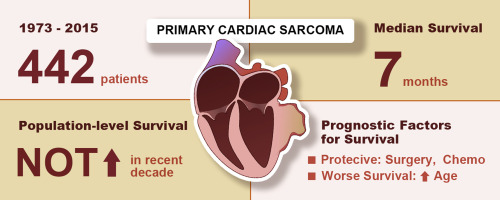

- มะเร็งหัวใจปฐมภูมิ (Primary cardiac cancer)

เป็นมะเร็งชนิดที่เกิดจากเนื้อเยื่อหัวใจโดยตรง ซึ่งเกิดได้กับเนื้อเยื่อทุกส่วนของหัวใจ เช่น เนื้อเยื่อที่กล้ามเนื้อหัวใจ เนื้อเยื่อที่เยื่อหุ้มหัวใจ เนื้อเยื่อบริเวณเยื่อบุหัวใจ เนื้อเยื่อพังผืด เนื้อเยื่อระบบประสาท เนื้อเยื่อไขมัน เนื้อเยื่อหลอดเลือดหัวใจ เป็นต้น โดยเป็นมะเร็งหัวใจชนิดที่พบได้น้อยมาก และมักไม่แสดงอาการใด ๆ ในระยะแรก

จากหลักฐานทางการแพทย์ ณ ปัจจุบัน พบว่า ทุกคนล้วนมีความเสี่ยงโรคมะเร็งหัวใจด้วยกันทั้งนั้น แต่อาจจะเสี่ยงมากหน่อยในผู้ชายอายุ 30-50 ปี ในขณะที่ความเสี่ยงของผู้หญิงก็มีอัตราส่วนที่ลดหลั่นลงมา นอกจากนี้ในกลุ่มคนที่สูบบุหรี่ หรือผู้ป่วยโรคเอดส์ ก็อาจมีความเสี่ยงเป็นมะเร็งหัวใจเพิ่มขึ้นได้ ในส่วนกลุ่มอาการที่พบจะได้แก่ หน้าบวม คอบวม หลอดเลือดดำที่คอโป่ง (กรณีเกิดมะเร็งที่หัวใจห้องขวาบน) หายใจไม่เต็มปอด อ่อนเพลีย เหนื่อยหอบ นอนราบไม่ได้ (กรณีเกิดมะเร็งที่หัวใจห้องซ้าย) หัวใจเต้นเร็ว เจ็บหน้าอก หน้ามืด วิงเวียน หรืออาจถึงขั้น หมดสติและหัวใจล้มเหลวเฉียบพลันได้

มะเร็งหัวใจที่เกิดโดยตรงเป็นมะเร็งที่มีเนื้อร้ายเกิดในผนังชั้นกลางของหัวใจ โดยเรียกว่า Angiosarcoma และ Rhabdomyosarcoma. มะเร็งหัวใจชนิดนี้ส่วนใหญ่ไม่ตอบสนองดีต่อการฉายแสงหรือเคมีบำบัด.

ในกรณีที่มะเร็งอยู่ในตำแหน่งที่สามารถทำการผ่าตัดได้ เช่น บริเวณผนังหัวใจด้านขวาบนและขวาล่าง แพทย์จะแนะนำให้รักษาด้วยการผ่าตัดเอาเนื้อร้ายออกให้หมด หากมะเร็งลุกลามมาที่หลอดเลือดแดงหัวใจ จะต้องผ่าตัดด้วยการต่อทางเบี่ยงหลอดเลือดหัวใจ เพื่อลดความเสี่ยงการเกิดกล้ามเนื้อหัวใจตายเฉียบพลัน หรือเลือกวิธีผ่าตัดเปลี่ยนลิ้นหัวใจให้ผู้ป่วยแทน ขึ้นอยู่กับดุลยพินิจของแพทย์ที่ทำการรักษา. การป้องกันโรคมะเร็งหัวใจยังไม่มีคำแนะนำที่ชัดเจน เนื่องจากสาเหตุที่ชัดเจนของโรคยังไม่ได้รับการรู้จัก สิ่งที่สามารถทำเพื่อลดความเสี่ยงในการเกิดโรคมะเร็งหัวใจได้คือ งดเครื่องดื่มแอลกอฮอล์ และงดสูบบุหรี่